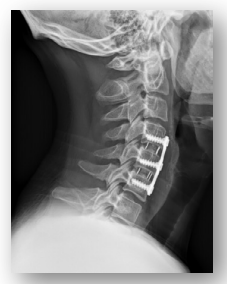

بعد إدخال التطعيم العظمي أو المادة الاصطناعية ، يمكن استخدام صفيحة معدنية أو مسامير لتثبيت الفقرات في مكانها أثناء شفاء الاندماج. تستغرق العملية عادةً حوالي ساعة إلى ساعتين ، ويمكن لمعظم المرضى العودة إلى المنزل في نفس اليوم أو في اليوم التالي.